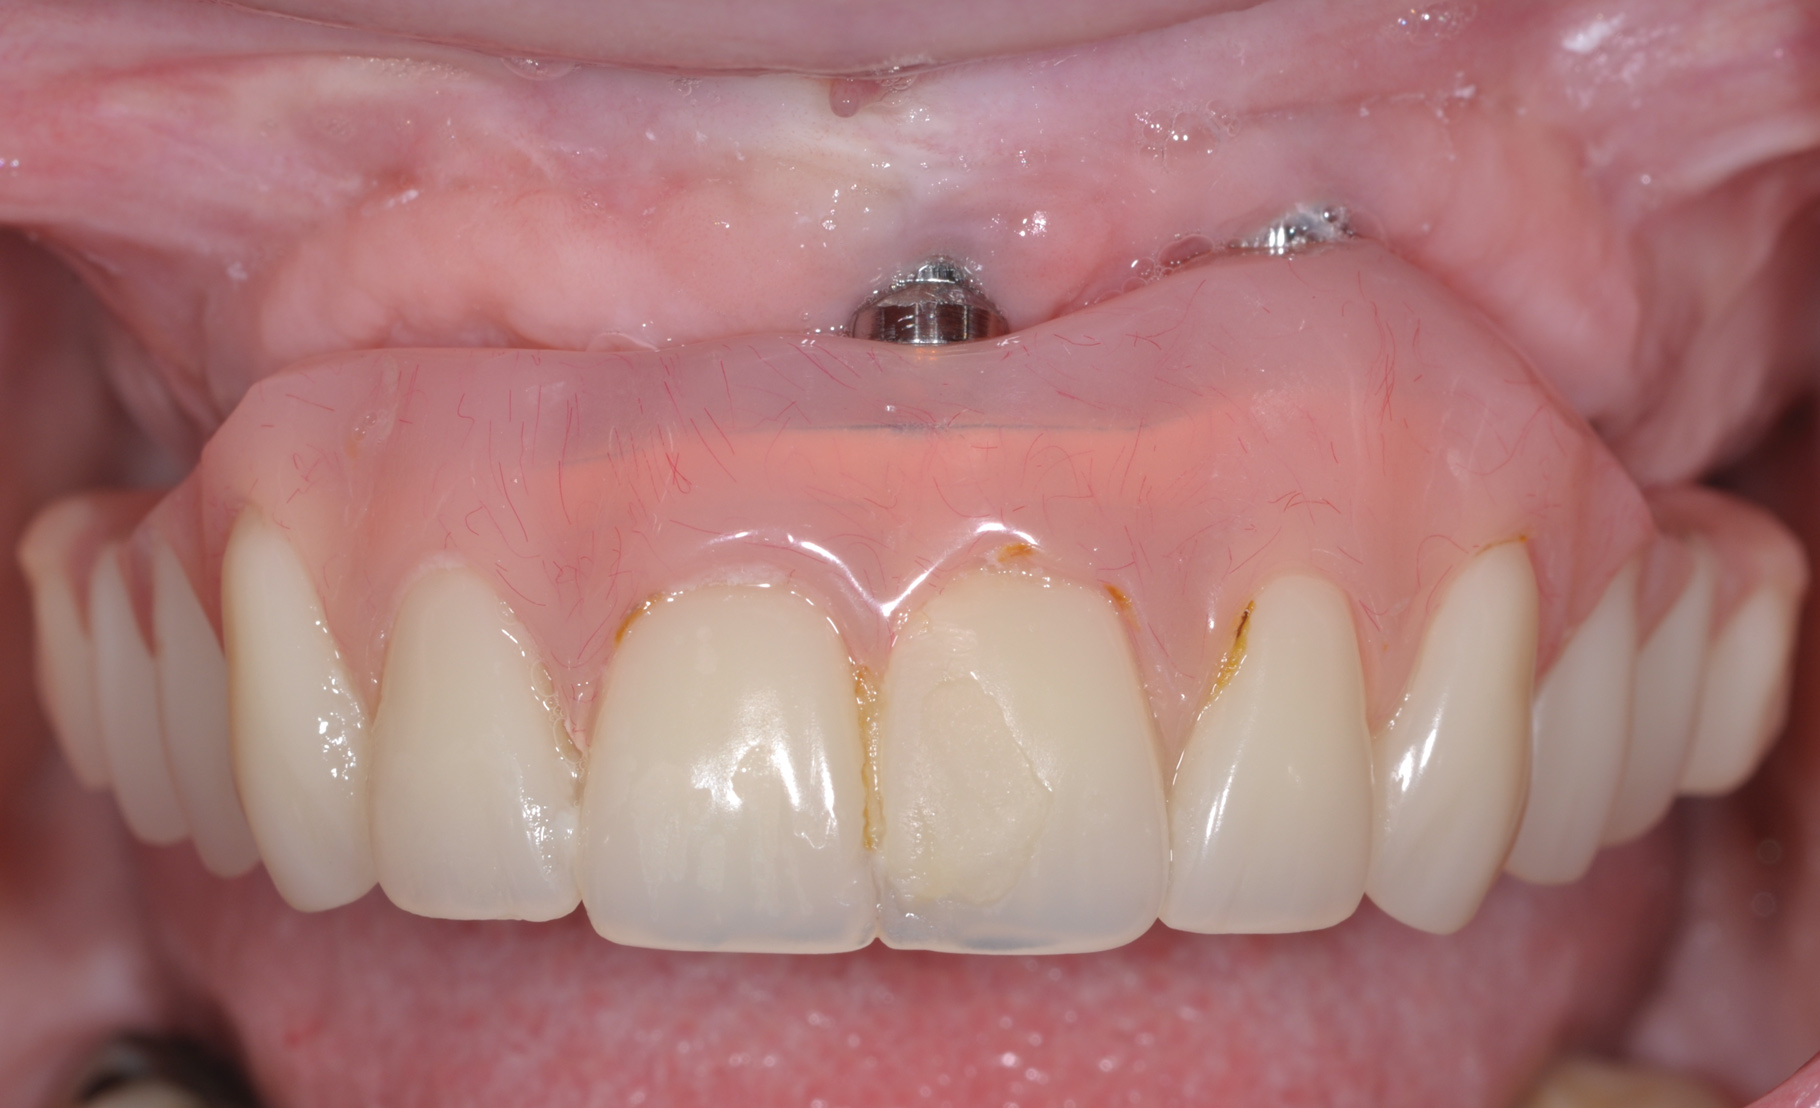

The main objective of peri-implant mucositis treatment is the resolution of inflammation.18 Oral healthcare providers should employ a two-pronged approach in the treatment of peri-implant mucositis. First, they should consider the patient's ability to perform adequate oral hygiene around the implant prosthesisthis includes assessing the patient's accessibility to the area in the mouthand prescribe appropriate aids in biofilm removal (Figure 1 and Figure 2). Second, the clinician should institute mechanical therapy and an appropriate peri-implant maintenance regimen consisting of further evaluation and treatment, if needed.

The clinician should review and reinforce with the patient the patient-administered oral hygiene efforts. Use of an intraoral stain to demonstrate inadequate plaque control has been shown to be effective in patient motivation.19 Nonsurgical peri-implant treatment should consist of mechanical removal of the bacterial biofilms and elimination or control of all local plaque retentive factors. Curettes, sonic and ultrasonic instruments, as well as air polishing with glycine powder are all effective methods of biofilm removal.20 The use of local antibacterials and local or systemic antibiotics appear to have minimal benefit.21 Once the treatment of peri-implant mucositis has been rendered, it is very important that the oral healthcare provider evaluate the response to therapy (Figure 3 and Figure 4). If initial therapy fails to resolve the peri-implant inflammation, it may be beneficial to assess the marginal fit and design of the implant prosthesis with regard to patient access, as well as the possible presence of cement remnants.

Fig 4. Four weeks after treatment, the patient presented with healthy peri-implant tissues.

Figure 4